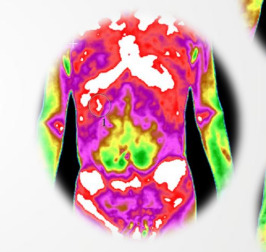

宋女士来我院进行TMT检测,在解读过程中发现其有乳腺导管扩张的可能,在为她解读报告后,她当即做了乳腺彩超,检查后发现确实有乳腺导管扩张。

TMT根据人体热度呈现出来的情况,可推断出出可能发生的疾病,从而达到早发现早预防或为下一步检查提供方向的目的。